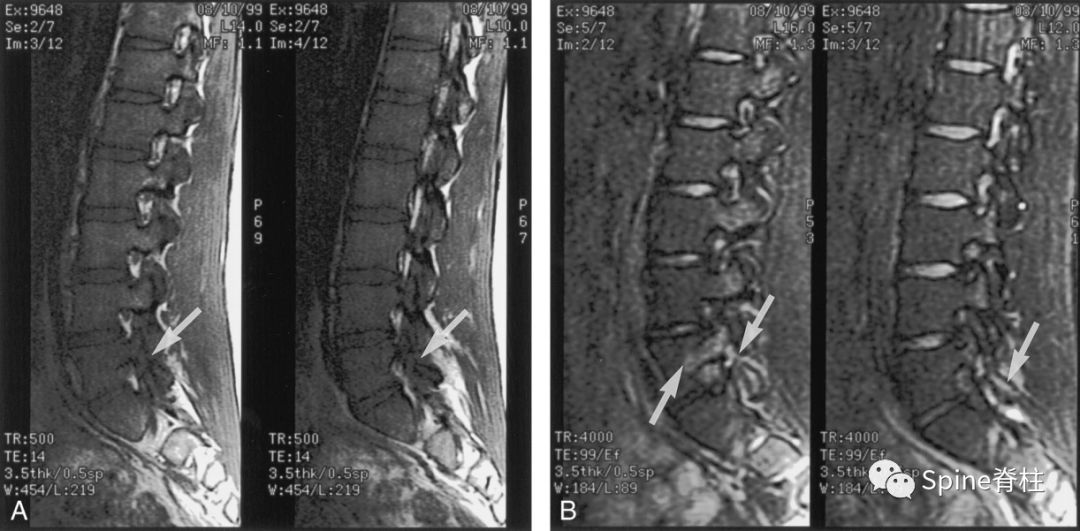

16岁的足球运动员诉右腰部疼痛。A:右侧T1加权像可见腰5峡部和椎弓根呈低信号(箭头);B:右侧T2加权像可见腰5峡部、椎弓根和关节突呈高信号(箭头)。

17岁的篮球运动员诉腰痛。A:T1像,左侧腰3峡部呈不连续的低信号(箭头);B:T2像,左侧腰3椎弓根和峡部呈高信号(箭头)

16岁的足球运动员,诉腰痛,以左侧为重。A:T1像可见腰5左侧峡部完全断裂(箭头);B:T2像,腰5左侧峡部、椎弓根和关节突水肿信号(箭头)

13岁运动员,左侧腰骶部疼痛。A:T1像,左侧腰5峡部完全断裂(箭头);B:T2像,左侧腰5峡部清晰可见,骨质无信号改变,峡部缺损处可见轻微的高信号,提示可能为肉芽组织或积液